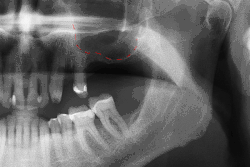

OPT vor externem Sinuslift und Implantation Regio 26 -